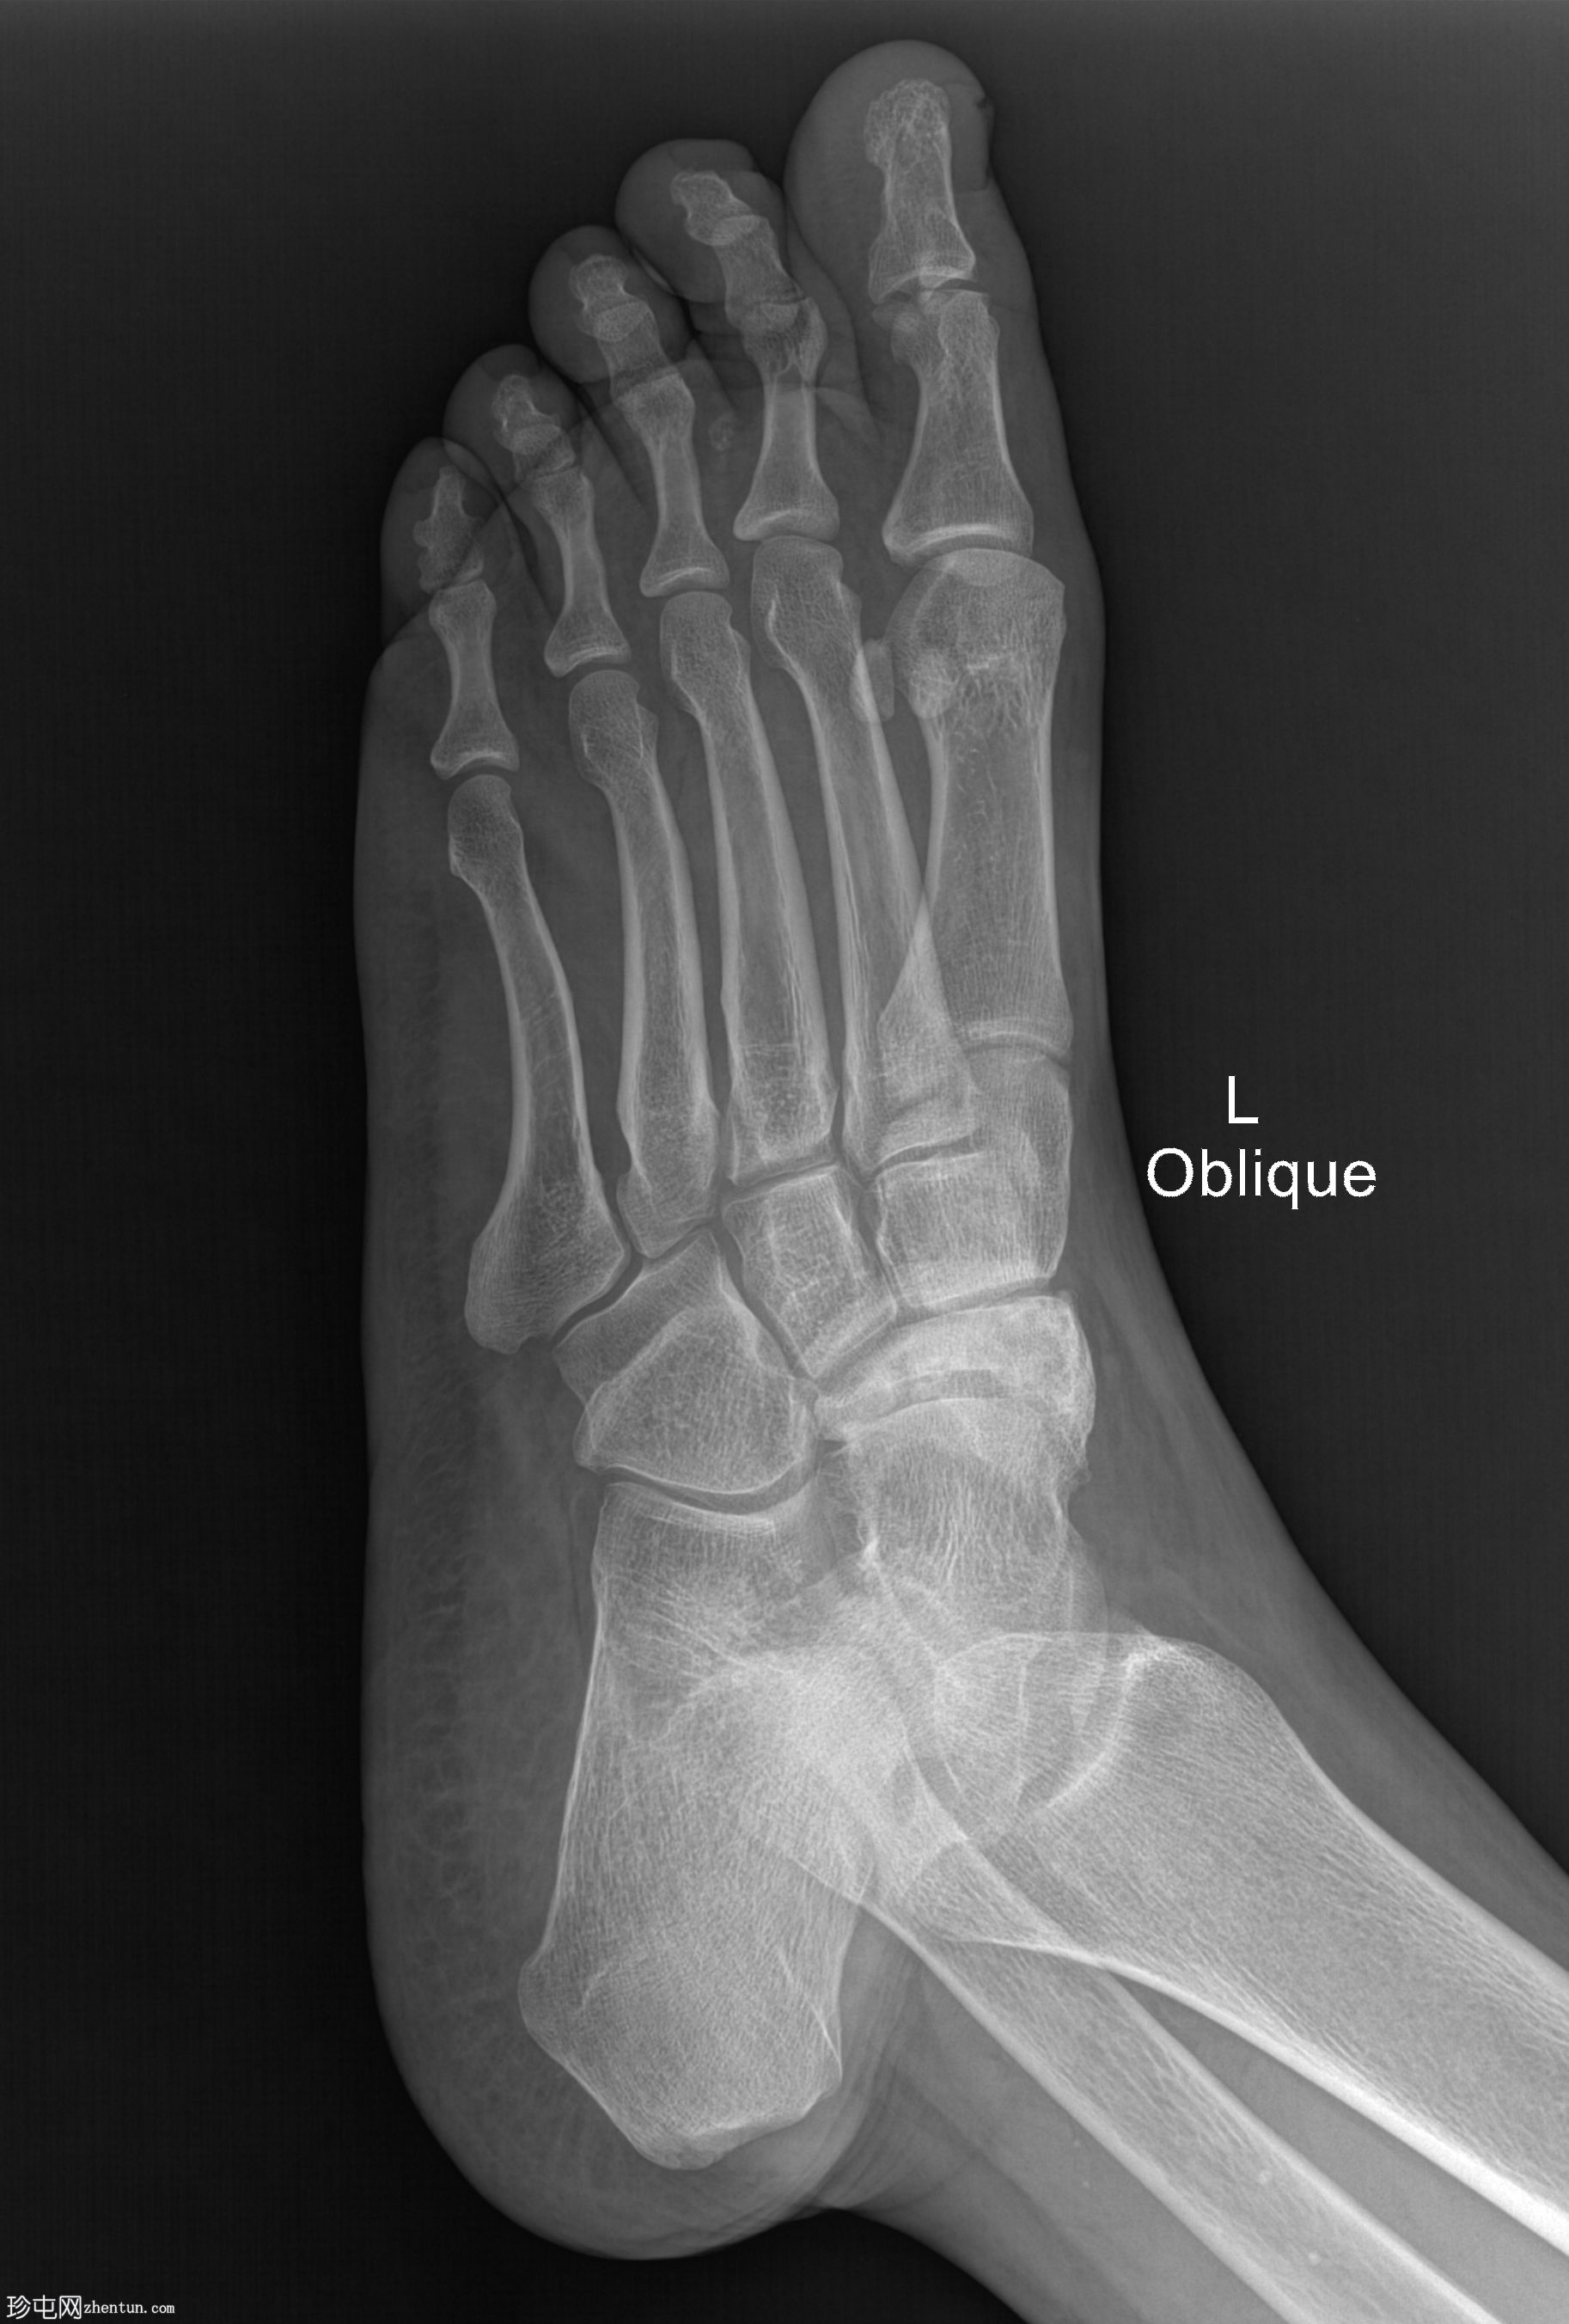

2.jpg

斜面

舟骨呈二分状,由较大的内侧骨块和较小的外侧骨块组成。

内侧骨块呈逗号形。

外侧骨块及其外侧可见斑块状硬化,提示慢性应力相关病变或软骨结合处退行性反应。

邻近的跗骨和关节间隙似乎保存完好。